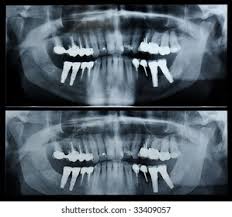

It is used to plan treatment for dental implants, check for impacted wisdom teeth and detect jaw problems.

HOWMANY X-RAY IN A FULL MOUTH SET :-

An FMX seriese of 18-20 x-rays which includes all 4 bitewings and PA’s of every tooth.